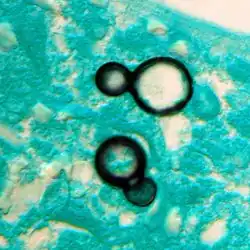

Once suspected, the diagnosis of blastomycosis can usually be confirmed by demonstration of the characteristic broad-based budding organisms in sputum or tissues by KOH prep, cytology, or histology.[27] Tissue biopsy of the skin or other organs may be required to diagnose extra-pulmonary disease. Blastomycosis is histologically associated with granulomatous nodules.